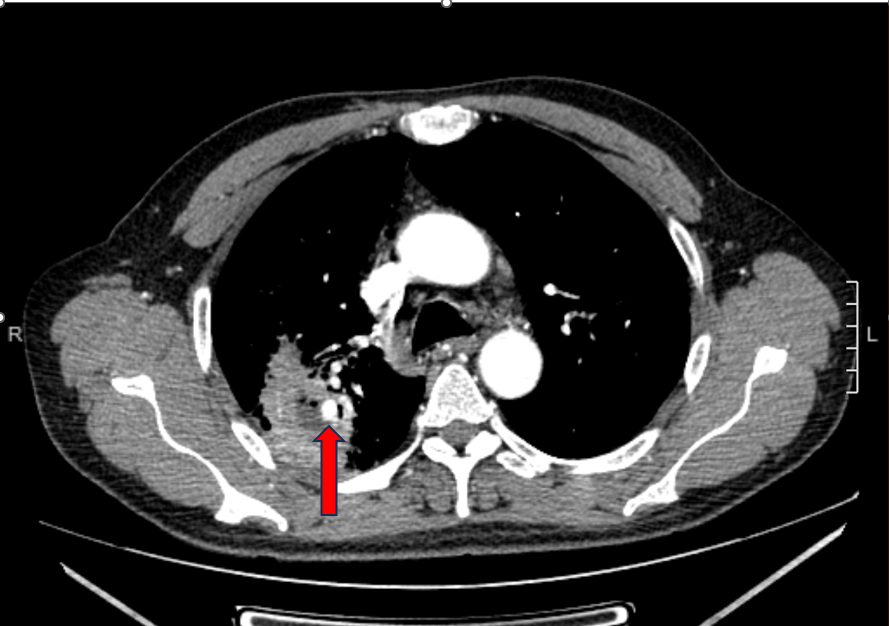

術(shù)前圖片:(紅色箭頭處為肺動(dòng)脈假性動(dòng)脈瘤)